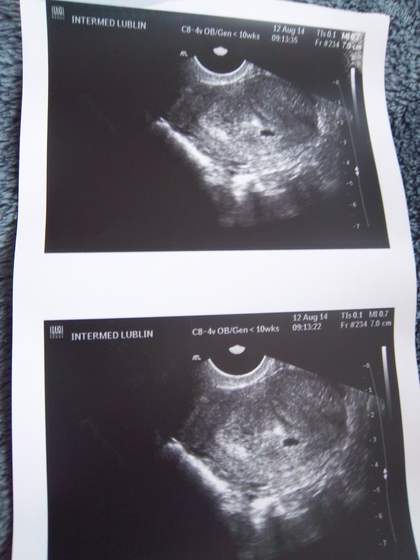

Hej dziewczyny wróciłam znad morza o 12 w nocy a rano miałam lekarza. Przedstawiam Wam moją fasolkę Jestem padnięta i raczej Was nie nadrobię teraz. Muszę nas wypakować i zrobić pranie, a strasznie mi się spać chcę bo się nie wyspałam.

Pytałam lekarza o kawę - powiedział, że można aby nie 8 dziennie ;p Mam nie zmieniać swoich nawyków żywieniowych drastycznie.

No a współżycie - powiedział, żeby się wstrzymać przez pierwszy trymestr. Dał mi skierowanie na badania i 26 mam przyjść znowu, żeby założył mi kartę ciąży.